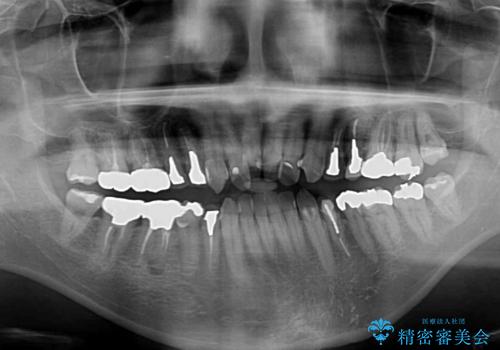

- 飛び出している上顎前歯と、奥歯に多くある銀歯を気にして来院された患者様です。

マウスピースで矯正を行いたい反面、一旦早めに前歯を整えたいというご希望があったため、まずは上顎前歯をワイヤー装置で整え、その後インビザラインにて仕上げていくこととしました。

矯正治療後には、奥歯の銀歯をすべてセラミックにて補綴治療することとしました。

補綴治療にあたり、痛みのある歯に対して根管治療を行うこととしましたが、処置が必要な歯が多かったため、期間を要しました。